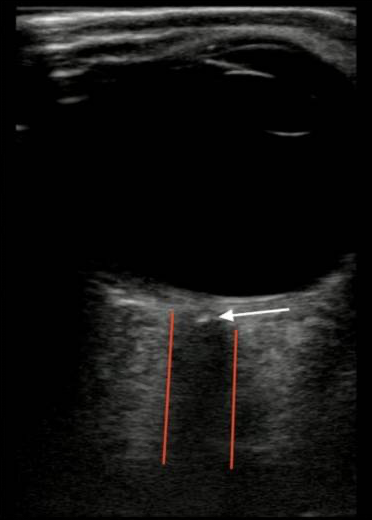

網膜中心動脈閉塞症(Central Retinal Artery Occlusion:CRAO)

Cozzi N, Stevens K, Pillay Y, et al. Diagnosis of Central Retinal Artery Occlusion in the Emergency Department Using POCUS: A Case Series. POCUS J. 2021 Nov 23;6:73-75.より引用

- カラードップラーを乗せることで動脈、静脈の血流を評価可能

- 視神経にSpot sign(Retrobulbar spot sign:RBSS)を認める場合がある

- RBSSを認めた場合にはCRAOに対して特異度100%